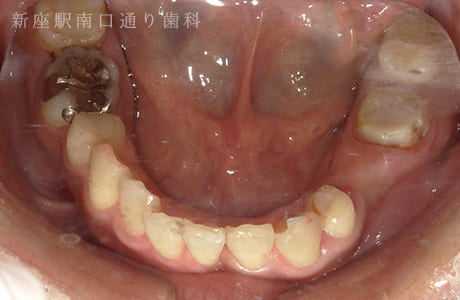

CASE.03

右下6番が破折抜歯後に

フルジルコニアブリッジで修復した症例

-

- 主訴

- 歯がないところを治したい

- 治療法

- 右下にフルジルコニアブリッジで修復

- 治療期間

- 1ヶ月半

- 費用

- ¥240,000(税込)

右下6番が破折し抜歯後にフルジルコニアブリッジで修復したです。

【リスク・副作用】

過度の咬合や衝撃で割れることがあります。治療直後は歯や歯茎に一時的な違和感や痛みが出ることがあります。